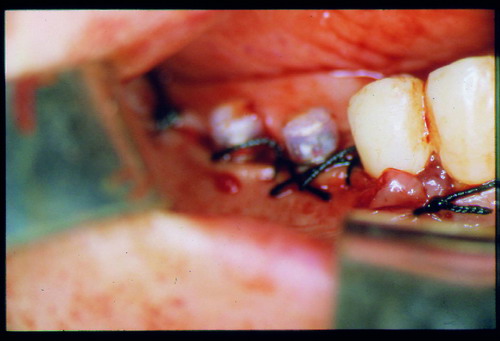

LA OCLUSIÓN MUTUAMENTE PROTEGIDA ES UN VIEJO CONCEPTO QUE CONSISTE EN LA MUTUA INTERACCIÓN DE LOS DISTINTOS GRUPOS DENTARIOS ENTRE SI. DE ESTA FORMA, LA TABLA PREMOLAR / MOLAR DE AMBOS HEMIMAXILARES ANTAGONISTAS, DETIENEN EL CIERRE MANDIBULAR EN CÉNTRICA, LOS CANINOS DISCLUYEN LAS PIEZAS POSTERIORES DURANTE LAS TRANSTRUSIONES, Y EL GRUPO INCISIVO LO MISMO DURANTE LAS PROPULSIVAS. SIN EMBARGO, DICHO CONCEPTO ES LIMITADO A LAS PIEZAS DENTARIAS, SIN TENER EN CONSIDERACIÓN LA IMPORTANTE FUNCIÓN QUE RECAE SOBRE LA ATM Y EN EL SOPORTE DE PRESIONES DURANTE ESTA DINÁMICA. ES ASI QUE EN EL AÑO 1981, EL DR. ANIBAL ALONSO GENERA EN LA CIUDAD DE BUENOS AIRES UN CONCEPTO MAS AMPLIO QUE DENOMINÓ : OCLUSION MUTUAMENTE COMPARTIDA. REF I EN EL QUE AMPLÍA EL CONCEPTO ANTERIOR, HACIENDO PARTÍCIPE A LA ATM EN LA MISMA. CUANDO EXISTE CARENCIA DE PIEZAS DENTARIAS POSTERIORES, YA SEA DE UN SOLO LADO O DE AMBOS , EL CIERRE MANDIBULAR ES DETENIDO POR LAS PIEZAS RESTANTE, FORZANDO A LA ATM A SOPORTAR PRESIONES MUY SUPERIORES A AQUELLAS PARA LAS QUE ESTA PREPARADA. FIG1 FIG2 FIG3 LUEGO DEL ESTUDIO CLÍNICO DE RIGOR, DONDE SE EVALÚA RADIOGRÁFICA Y PERIODONTALMENTE, SE PROCEDE A TOMAR MODELOS DE ESTUDIO Y MONTAR EN ARTICULADOR SEMIAJUSTABLE, SOBRE EL CUAL SE REALIZA UN ENCERADO PROGRESIVO DE DIAGNÓSTICO, A PARTIR DEL CUAL SE CONFECCIONA UN JUEGO COMPLETO DE PROVISIONALES DE AMBAS ARCADAS , INCLUYENDO LAS PIEZAS FALTANTES. SE ABORDA EL CASO YA QUIRÚRGICAMENTE DONDE EN UNA PRIMERA ETAPA SE TALLAN PRIMARIAMENTE LAS PIEZAS DENTARIAS Y SE PROCEDE, EXODONCIANDO EL INCISIVO CENTRAL SUPERIOR DERECHO, A REALIZAR UNA ROG(REGENERACIÓN ÓSEA GUIADA), PARA INMEDIATAMENTE INSTALAR PARTE DE NUESTROS PROVISORIOS EN LA GUIA ANTERIOR. SE ADAPTAN A LOS SECTORES POSTERIORES LAS PRÓTESIS REMOVIBLES QUE PORTABA, Y SE ESPERAN CUATRO MESES, AL CABO DE LOS CUALES SE REALIZA UN ESTUDIO CON DENTASCAN, MEDIANTE EL USO DE UNA FÉRULA RADIOLÓGICA CON TUBOS METÁLICOS , QUE NOS SERVIRÁ TAMBIÉN DE GUÍA QUIRÚRGICA. PROCEDEMOS ENTONCES A LA IMPLANTACIÓN DE LOS SECTORES EDÉNTULOS MEDIANTE IMPLANTES ROSCADOS Y TÉCNICA SEMI SUMERGIDA. TRANSCURRIDAS OCHO SEMANAS OBSERVAMOS UNA CORRECTA SALUD PERIMPLANTARIA, Y REALIZAMOS LA INSTALACIÓN DE LOS ABUTTMENTS ALCANZAMOS ENTONCES EL PUNTO EXACTO DONDE DEBEREMOS COMENZAR A RECONTRUIR EN FORMA PERMANENTE. PAZ DEL SISTEMA: CENTRICIDADARTICULAR-PAZ MUSCULAR-ESTABILIDAD- -ACOPLAMIENTO. BASES FUNDAMENTALES DE LA OCLUSIÓN ORGÁNICA FIG41 FIG42 PROCEDEMOS NUEVAMENTE A TOMAR IMPRESIONES, EN ESTE CASO DEFINITIVAS , MONTAR NUEVAMENTE EN ARTICULADOR, Y CONSTRUIR LAS RESTAURACIONES PERIFÉRICAS TOTALES EN BASE A PORCELANA SOBRE ORO GALVANIZADO. REF. II SOBRE LAS MISMAS TERMINADAS Y YA EN BOCA, CHEQUEÁMOS TODOS LOS ELEMENTOS QUE CONSTITUYEN UNA REHABILITACIÓN ORAL INTEGRAL, DESDE LA SALUD ENDODONTICA DE PIEZAS TRATADAS O NO, LA SALUD PERIODONTAL, EL AJUSTE PERIFÉRICO DE LAS RESTAURACIONES, LA ESTABILIDAD EN LA ATM, Y LAS FUNCIONES OCLUSALES, CHEQUEOS ESTOS QUE SE REPETIRAN EN CADA UNO DE LOS CONTROLES POST OPERATORIOS. FIG46 FIG47 FIG48 FIG66 FIG67 REFERENCIAS: REF I: OCLUSIÓN Y DIAGNÓSTICO EN REHABILITACIÓN ORAL REF. II ELECTROFORMACIÓN EN ODONTOLOGÍA RESTAURADORA.